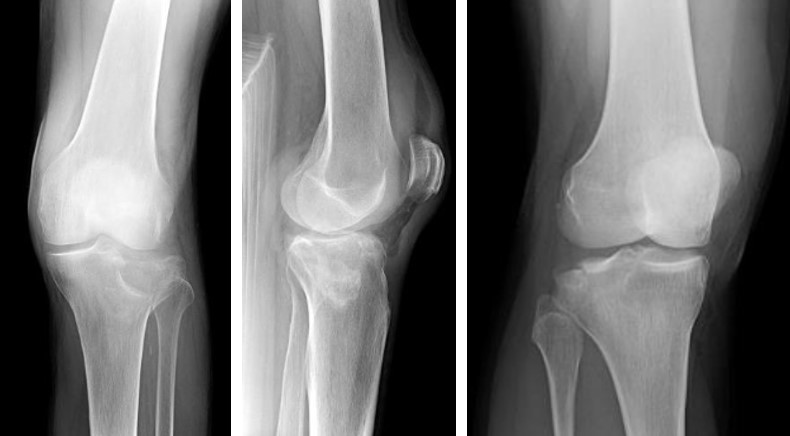

Променева діагностика переломів проксимального відділу кісток гомілки

Рентгенографія у трьох проекціях є первинним методом діагностики, проте часто недостатньо інформативна для оцінки характеру внутрішньосуглобового перелому.

Пряма, бокова, коса проекції

Комп’ютерна томографія (КТ) з тривимірною реконструкцією є золотим стандартом діагностики. Вона дозволяє точно визначити характер перелому, ступінь зміщення, кількість та розміри фрагментів, стан суглобової поверхні та планувати хірургічне втручання.

Магнітно-резонансна томографія (МРТ) показана для оцінки супутніх ушкоджень зв’язкового апарату, менісків, хрящової тканини та кісткового мозку: